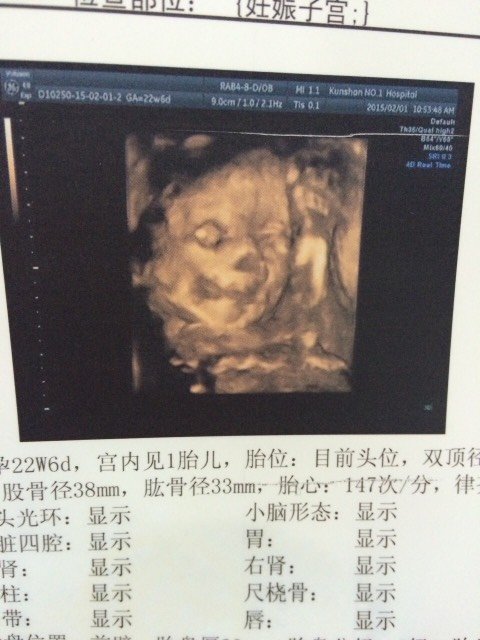

有没有专业人士解答,为什么我宝宝三维彩超的嘴巴边上那块是黑色的,是不是胎记呀,嘴巴和鼻子都看不清

你好,胎儿四维彩相则泳超是看不到胎儿脸上的胎记的,黑色的可能是其他的遮挡物造成的阴影,嘴巴和鼻子显示的不算很清晰,跟倘常胎儿在宫内的姿势有关,只要B超大夫说斯射没问题就行。